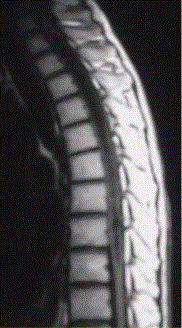

问题 患者女,45岁,胸部不适。影像学检查结果如下图所示。 关于成血管细胞瘤,正确的是

选项 A.脊髓内肿瘤 B.X线检查无阳性发现 C.明显增强的血管性壁结节对定性诊断价值 D.可多发,并伴发von-Hippel-lindau综合征 E.肿瘤上下或肿瘤内区域内见葡状生长的流空信号,可以确诊 F.发病率较低